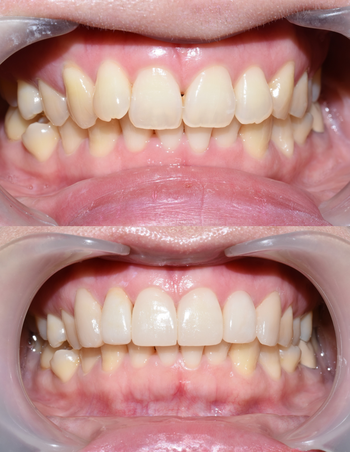

윗니 라미네이트5개와 크라운 전후 입니다.

윗니 라미네이트5개와 굉장히 많이 튀어나온 치아 1개 크라운으로 자연스럽고 고른 치아가 되었습니다.